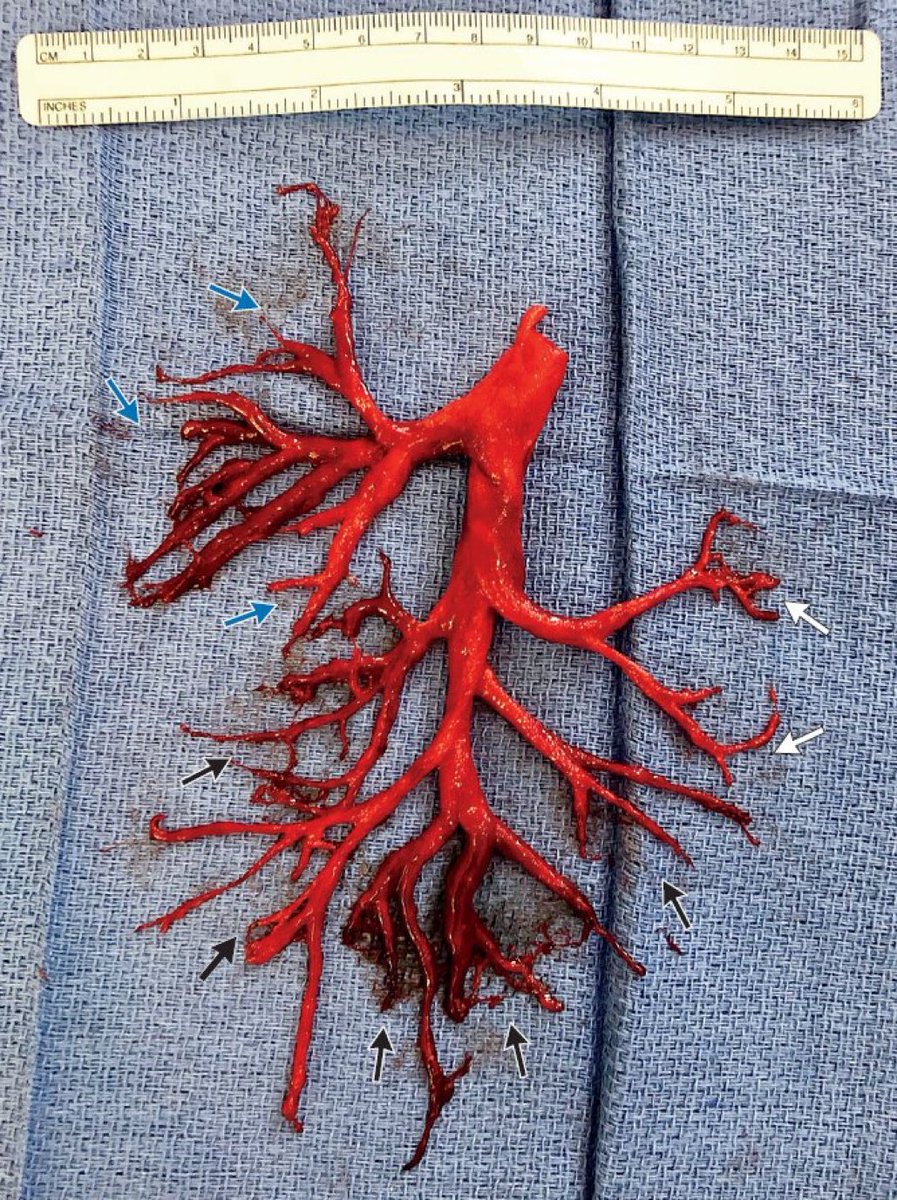

Avraham Z. Cooper, MD 🩺 Cannon ball app in lung via hematogenous spread Choriocarcinoma..raised hcg levels Other signs- • hyperthyroidism( as alpha subuit of hcg~ TSH,Lh,fsh) •Gynecomastia D/D: CRASH C- CHORIOCARCINOMA R- RCC A- ADRENAL S- SYNOVIAL SARCOMA H- his- prostate Her- endometrial